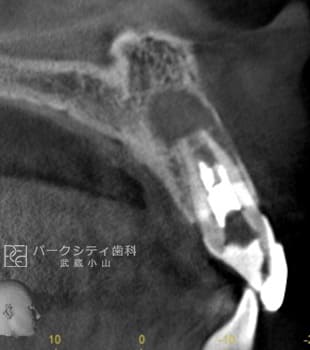

ルートメンブレンテクニックを併用した前歯部抜歯即時埋入の症例

ルートメンブレンテクニックとは歯根を一部温存することにより、顎堤の吸収を抑止することができるため審美的によい結果が得られます。また、今回大きな切開や移植などしていないため腫れや痛みも少なく、治療期間も短くてすみます。